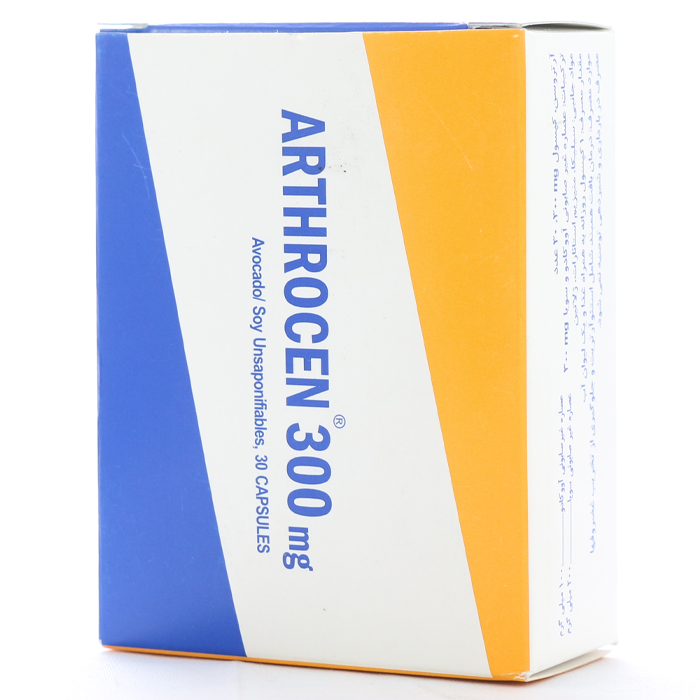

کپسول آرتروسن 300

کپسول آرتروسن، با احتوای عصارههای آووکادو و سویا، از فرآیند تخریب غضروفها جلوگیری میکند و به عنوان یکی از بهترین راهکارها برای درمان آرتروز شناخته میشود.

کپسول آرتروسن با بهبود تغذیه بافت همبند، از تخریب غضروفها پیشگیری میکند و منجر به بهبود ساختار استخوانها میشود. کپسول آرتروسن، با خاصیت ضد التهاب و بدون حاوی مواد نگهدارنده، یکی از داروهای استثنایی برای کاهش پیشرفت استئوآرتریت محسوب میشود.

علاوه بر این، مصرف کپسول آرتروسن باعث افزایش قدرت حرکت مفاصل میگردد و همچنین تخریب کلاژن را مهار و سنتز آن را تحریک میکند. جهت آشنایی بیشتر با بیماری استئوآرتریت، در ادامه با ما همراه باشید.برای تهیهي کپسول آرتروسن به داروخانه آنلاین دارونت مراجعه فرمایید.

جدول ترکیبات کپسول آرتروسن

| ترکیبات | مقدار در هر وعده روزانه |

| عصاره غیر صابونی آووکادو و سویا | ۳۰۰mg |

| عصاره غیر صابونی آووکادو | ۱۰۰mg |

| عصاره غیر صابونی سویا | ۲۰۰mg |

| سیلیکا | ۷,۵mg |

| منیزیم استئارات | ۷,۵mg |

| ژلاتین | ۳۵mg |

چطور مصرف کنیم

روزانه یک عدد کپسول آرتروسن به همراه غذا و همراه با آب فراوان میل شود.